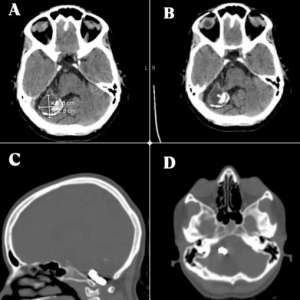

Огромная аневризма у беременной

Беременная, 23 года

Настоящая беременность вторая, на 28-й неделе обратилась к врачу с жалобами на периодические головные боли, которые значительно усилились за последние три дня. Головная боль стала невыносимой, отдавала в шею и сопровождалась многократной рвотой и выраженной светобоязнью.

Примечательно, что после рождения первого ребёнка два года назад она была госпитализирована на месяц из-за постоянных головных болей и лихорадки, МРТ головного мозга не выполнялось. До недавнего времени её текущая беременность протекала без осложнений.

У пациентки не было в анамнезе гипертонии, диабета или заболеваний соединительной ткани. Она не принимала никаких препаратов и не употребляла алкоголь и табак.